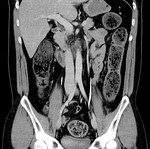

[画像診断]閉塞性大腸炎について(宿便が原因である可能性) 2011-05-12